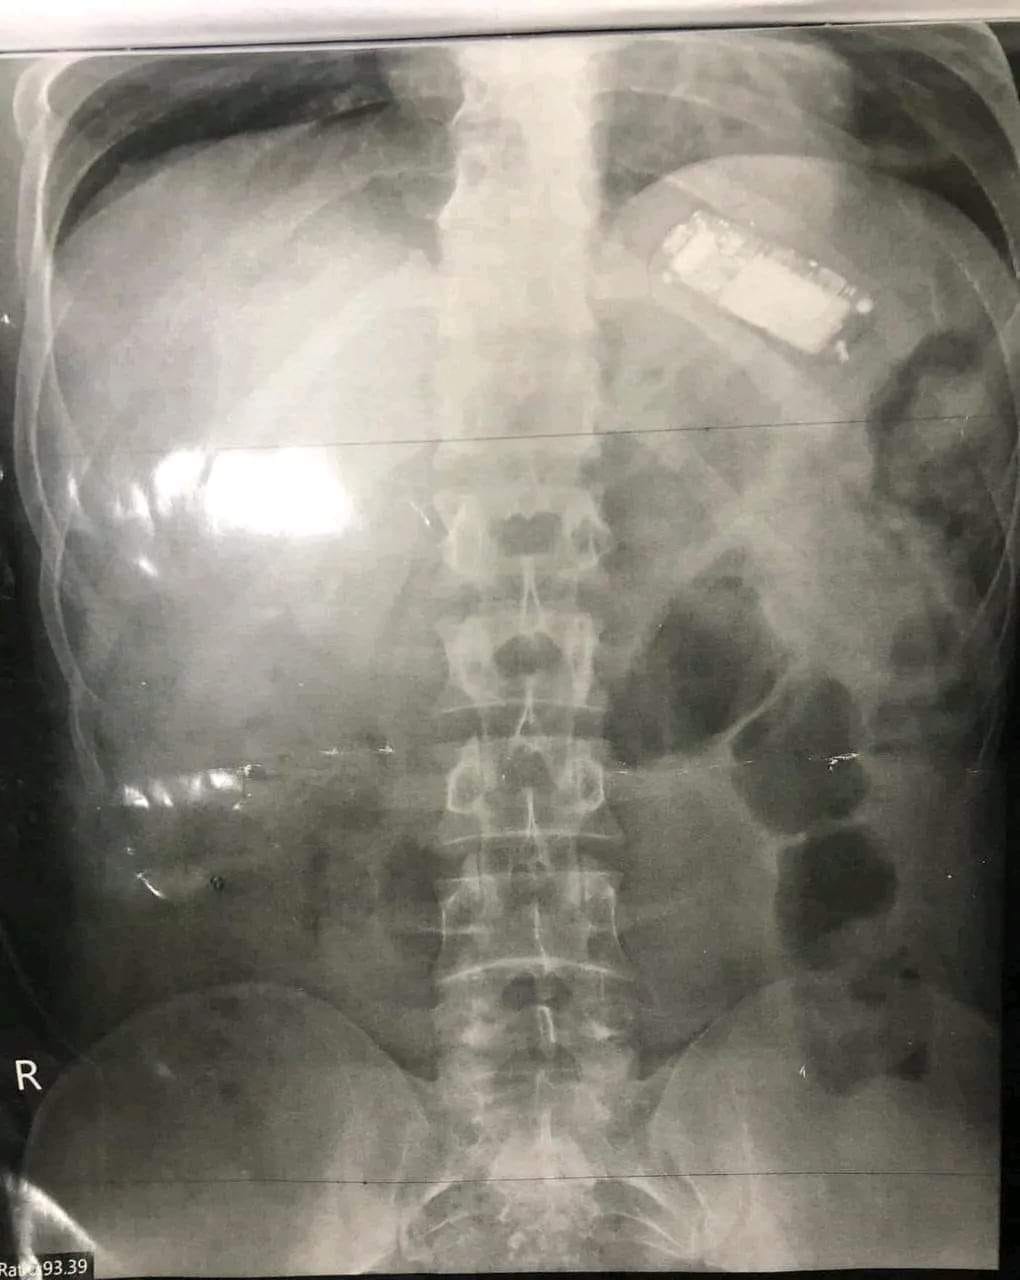

تمكن فريق طبي بمستشفى الباطنة التخصصي بجامعة المنصورة بمحافظة الدقهلية، اليوم، من استخراج موبايل «تليفون محمول» كبير الحجم من بطن شاب باستخدام المنظار الطبي، بعد أن ابتلع الشاب الهاتف المحمول، وظل داخل معدته لأكثر من شهرين وعانى من آلام شديدة وفقدان للوزن، إلى أن حضر إلى المستشفى.

وتبين أن المريض أجريت له عدة محاولات لاستخراج التليفون في مراكز طبية خاصة إلا أنها لم تنجح، وكان منظار اليوم المحاولة الأخيرة قبل أن يتدخل الأطباء جراحيا لاستخراج التليفون.